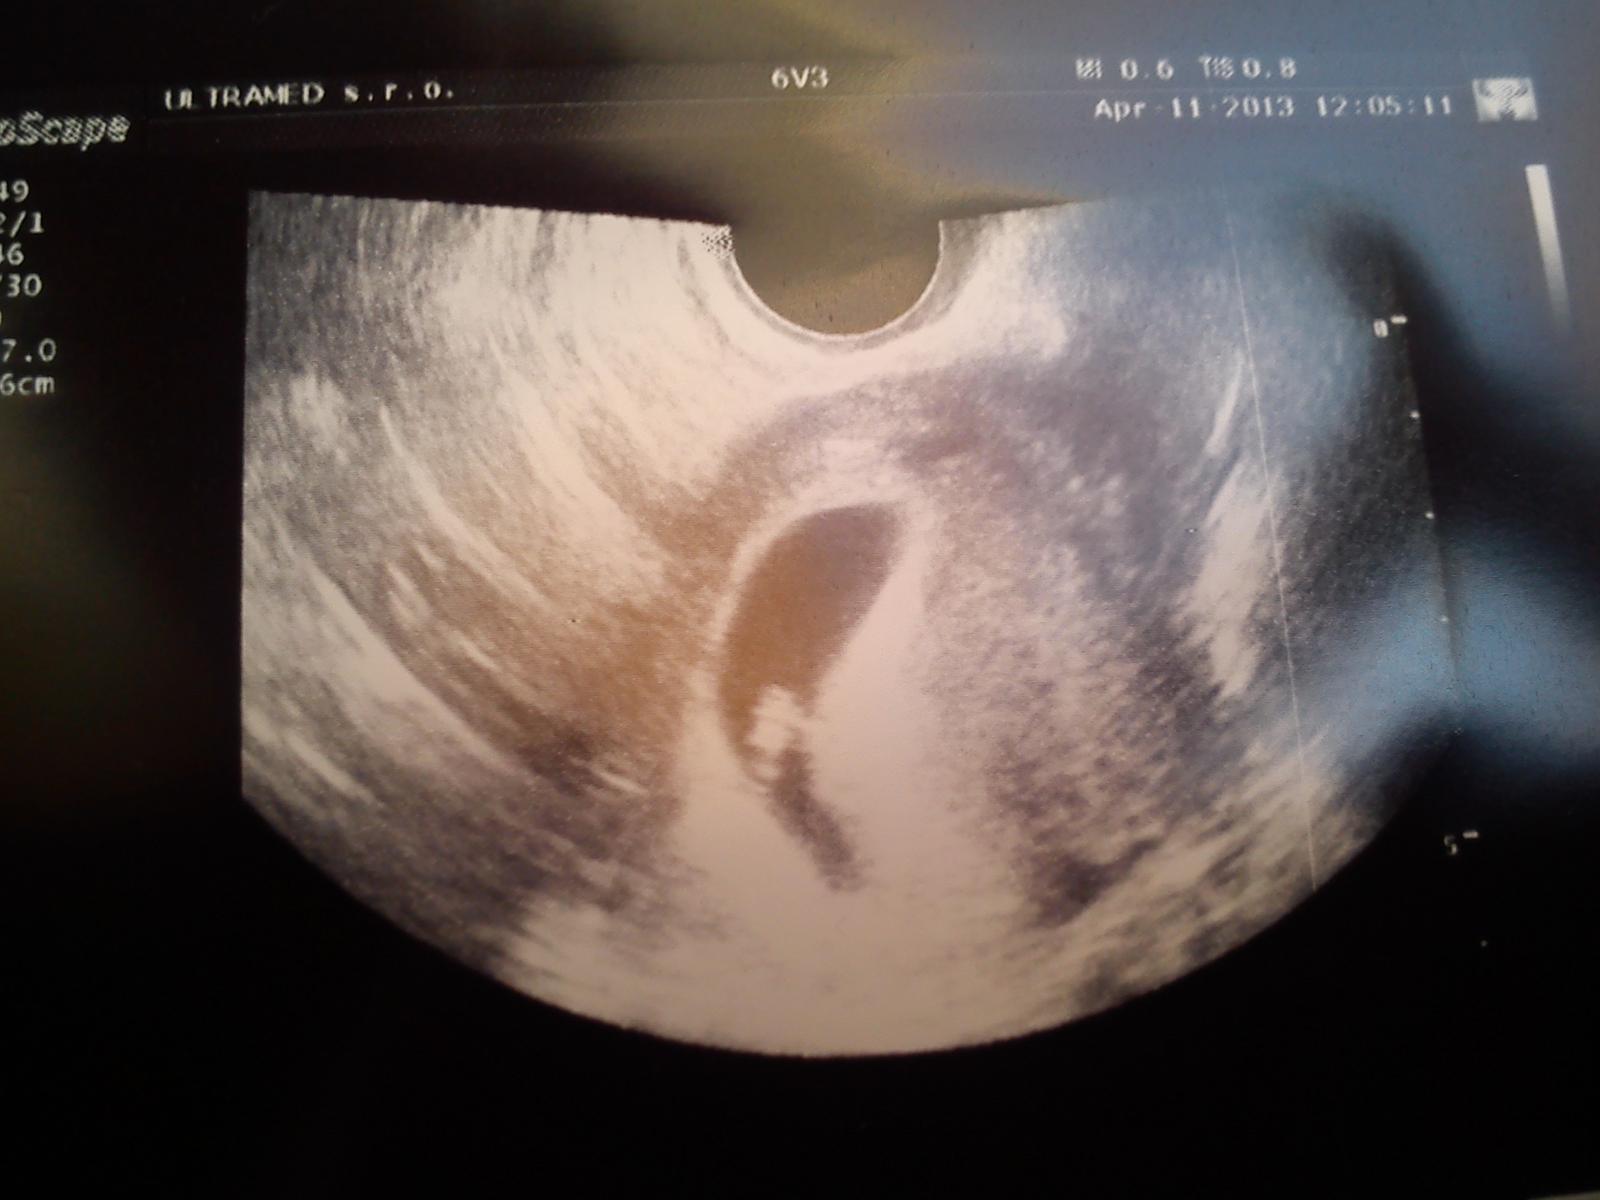

Ahojte.tak som bola dnes u doktora,vsetko je tam kde ma byt 🙂 som 7+2tt babo ma 10,8mm a srdiecko krasne bilo.termin mi este nedal,idem za tri tyzdne na prvu poradnu+krv a moc a tam sa uvidi ako babo rastie a az potom urci presny termin.ked mala zaspi hodim aj fotecku.

Ahojte. Tak sa oficialne od dnes pridavam k Vam. Bola som dnes u dr. a vsetko v poriadku. Babo ma 0,59 cm. Mala by som byt 7+2 ale velkostne zodpoveda 6+3. Prve tehotenstvo som mala rizikove, mala som placentu praevia marginalis, tak dufam, ze tento krat bude vsetko v poriadku. Aj dr ma utesovala, ze raz stacilo.. Tak nam vsetkym drzim palce. Pekny dnik